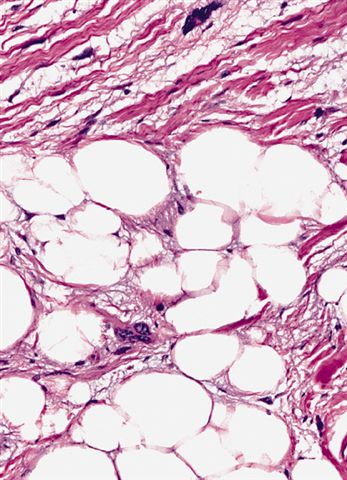

Microscopic (histologic) images

Contributed by Michael Clay, M.D., Melanie Bourgeau, M.D. and AFIP

Morphologic variability:

Metaplastic change:

- Depends on subtype, generally composed of mature fat with variably sized adipocytes and bands of fibrotic stroma containing spindle cells with enlarged, hyperchromatic nuclei

- Can be markedly atypical

- Cellularity is low and mitotic figures are uncommon

- Atypical cells are more commonly found in fibrous septa and in a perivascular distribution

- Typically multilobulated and well circumscribed

- Rarely are grossly infiltrative

- Marbled yellow cut surface in lipoma-like lesions, with more firm / fibrotic white areas grossly in lesions with less adipocytic differentiation (Semin Diagn Pathol 2019;36:112)